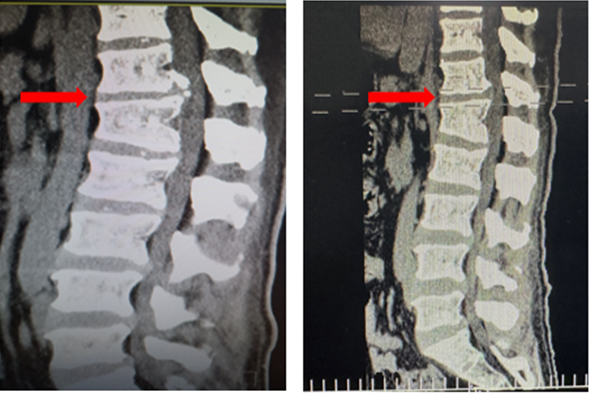

患者术前(左)及术后(右)影像学资料